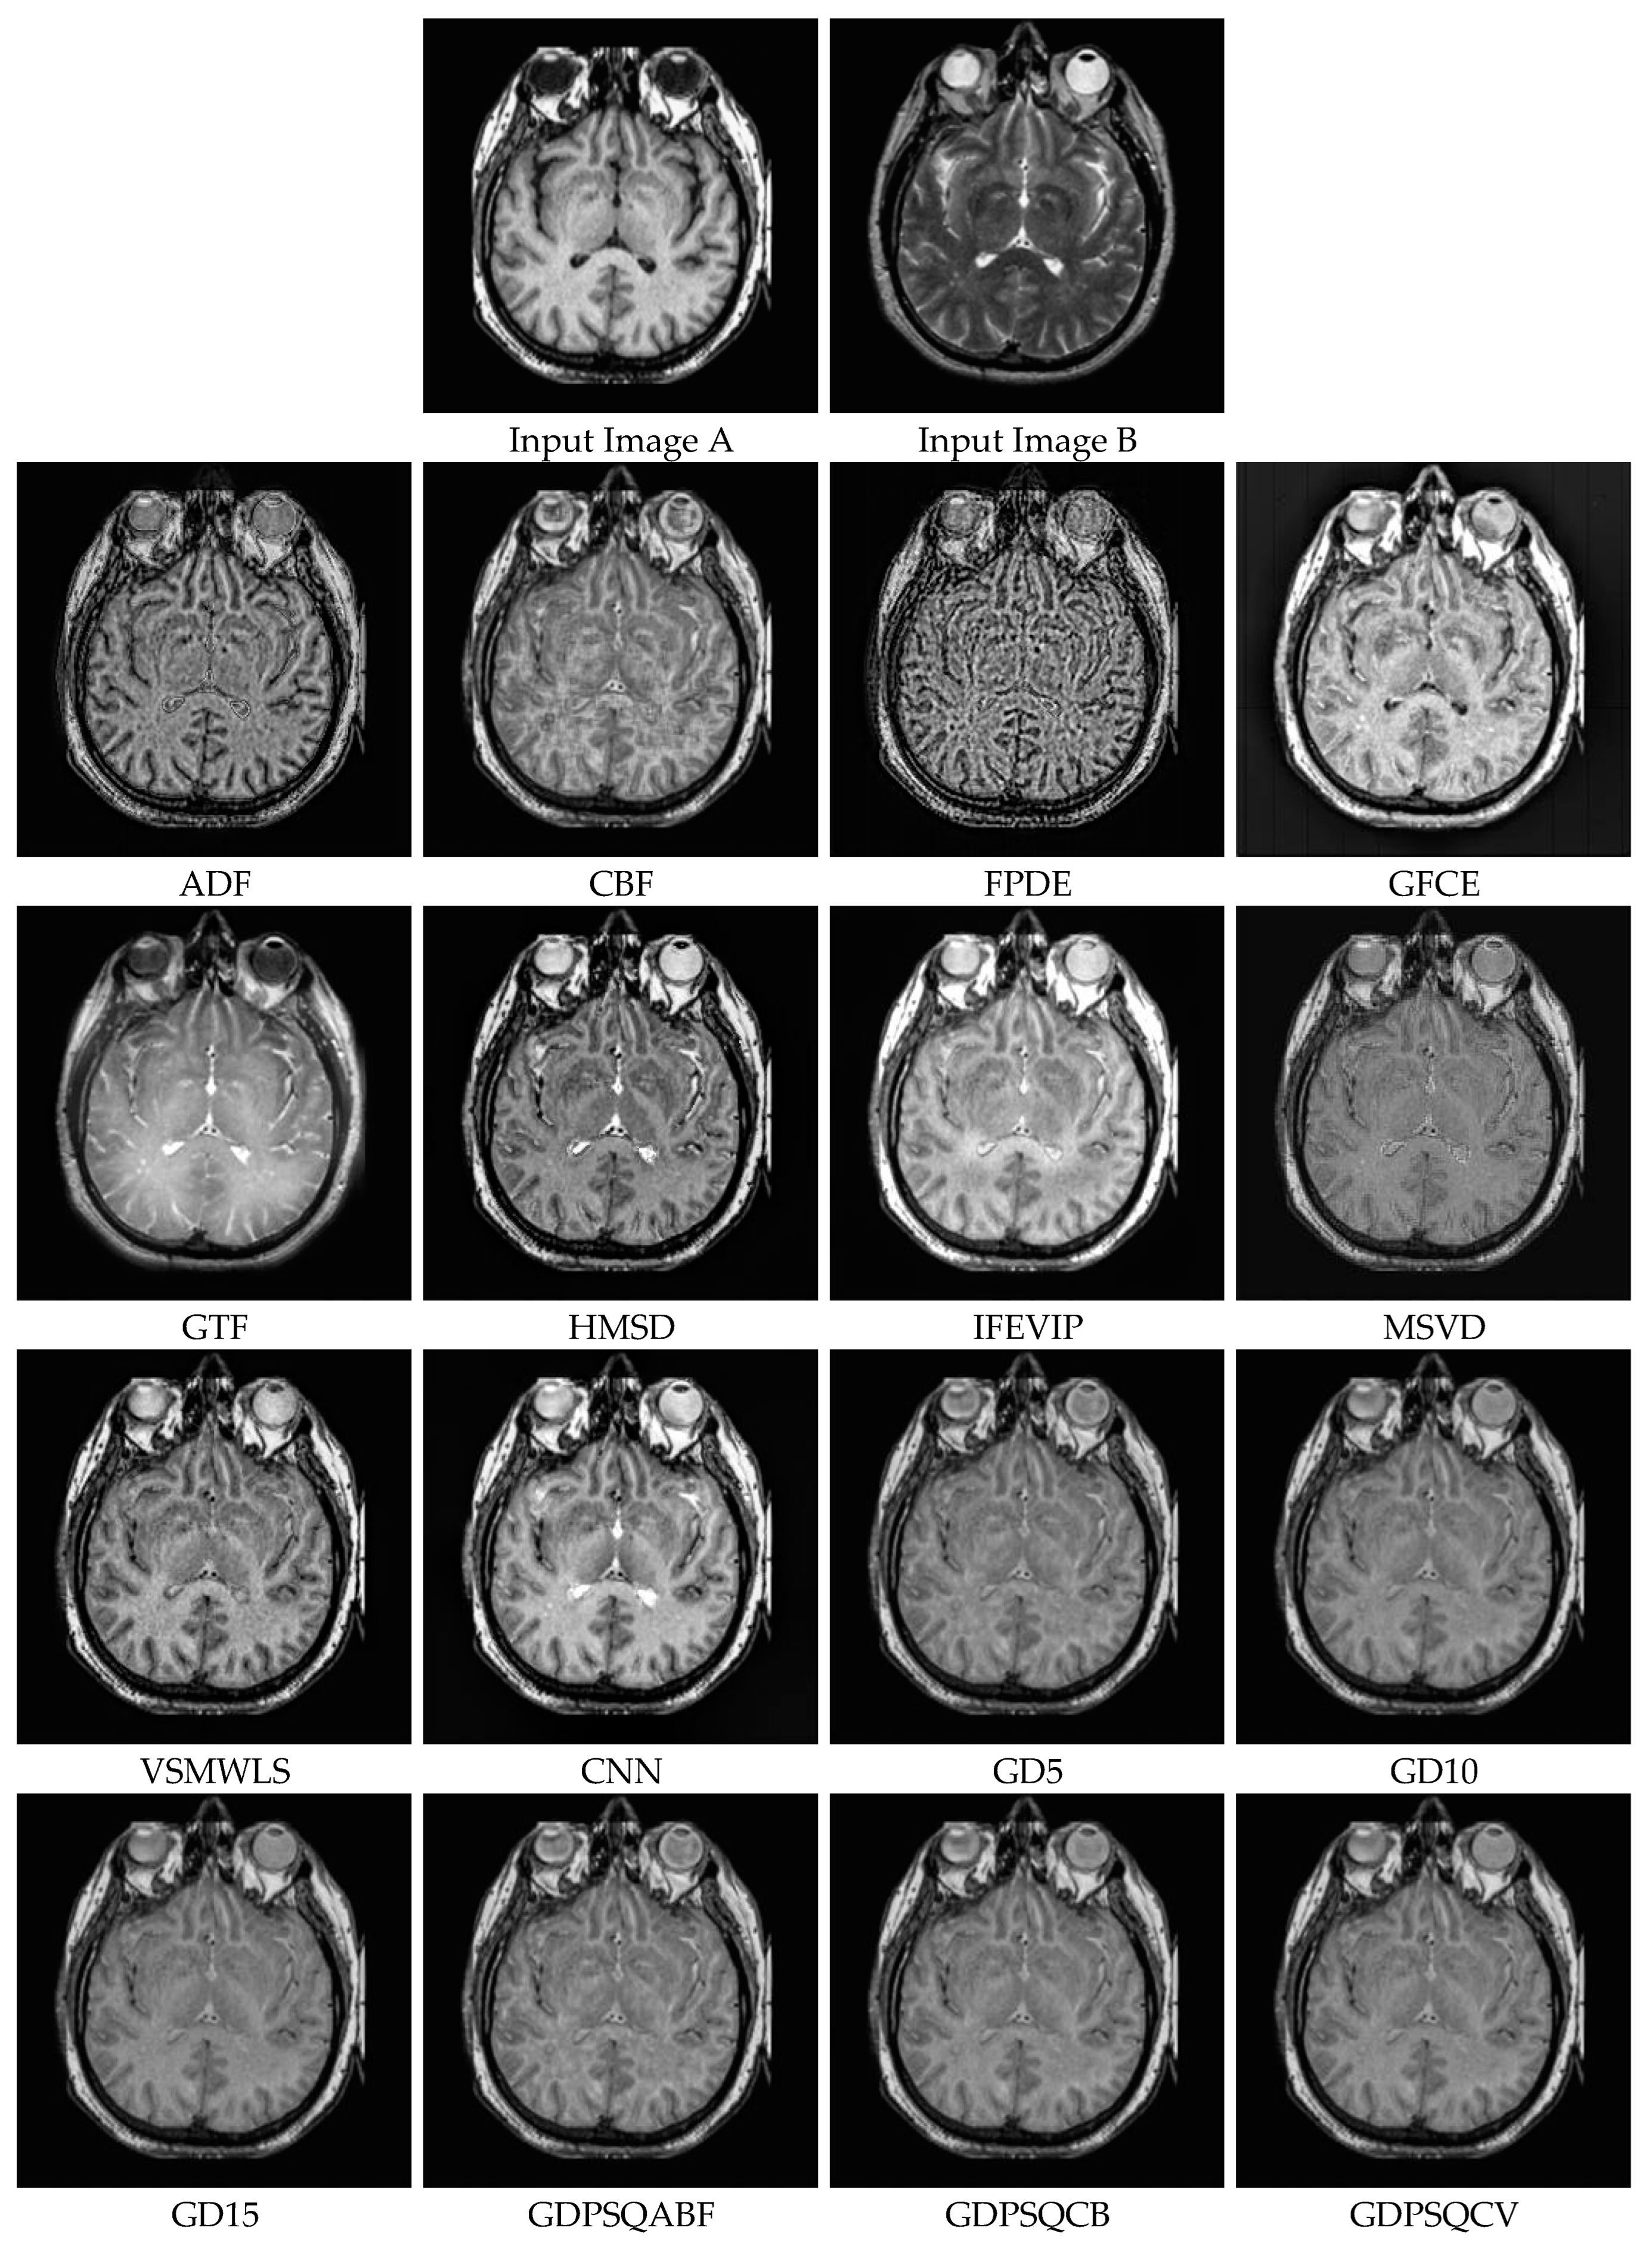

The results of the image set M#5 are given in Figure 14. As can be seen from the results, ADF, FPDE, GFCE and MSVD show poor visual performance. On the other hand, the CBF, VSMWLS, and proposed GD methods show better visual performance than other techniques.

In Table 5, the numerical results of the quality metrics of the comparison methods for M#5 are given. As can be seen in Table 5, the CNN, proposed GD10, and proposed GDPSQCV methods show better performance according to the numerical results. On the other hand, MSVD, FPDE, and GFCE show the worst performance compared to the others.

Figure 14. Medical image set M#5 (Images A and B) and their fusion image results, obtained using comparison methods.

Entropy 25 01215 g014